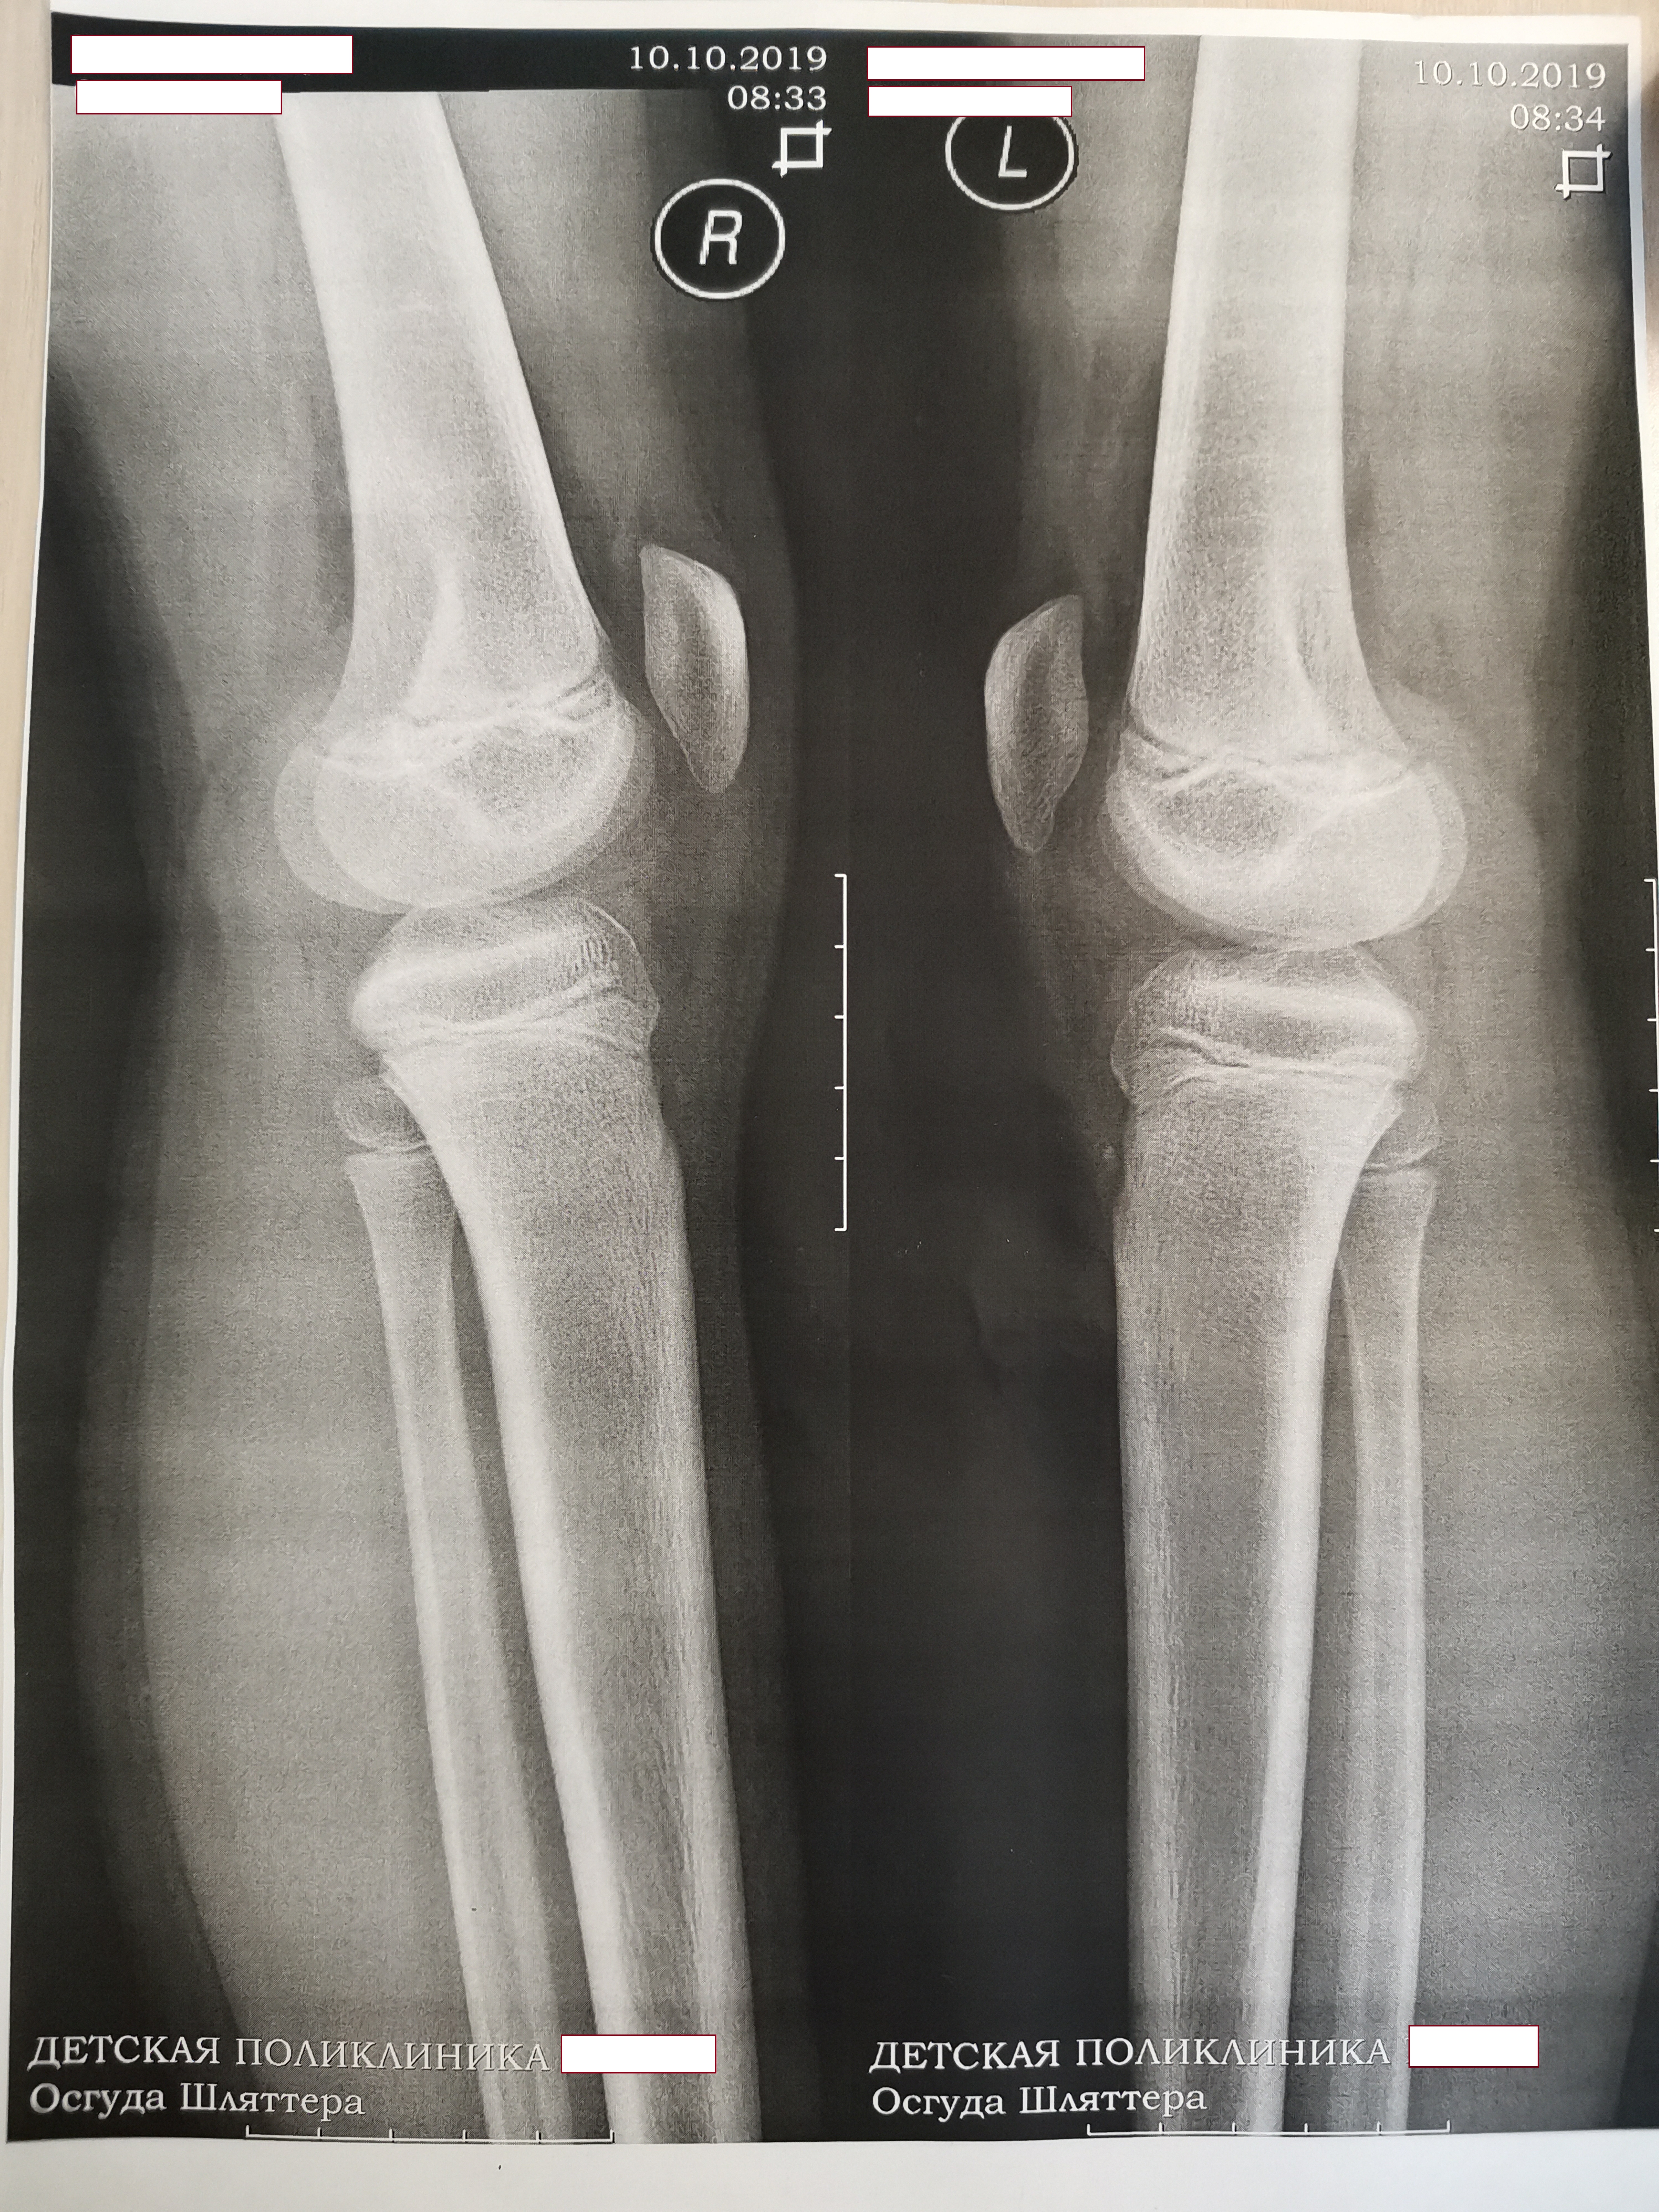

Осгуда Шляттера

Здравствуйте! Подскажите пожалуйста, в нашей поликлинике дочке поставили диагноз Осгуда Шляттера, ей почти 10 лет (через пару месяцев), занимаемся танцами, нагрузки не очень большие, в данный момент ехать на обследование нет возможности, но не хочется упустить момент. Верно ли поставили диагноз, судя по снимку? Спасибо!

ПРизнаков болезни Шляттера не нахожу.